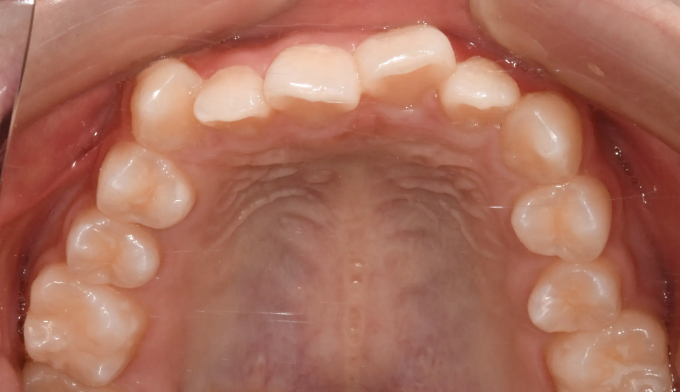

주걱턱, 그리고 앞니가 거꾸로 물리는 ‘반대교합’은 비슷한 말이 아닙니다. 서로 전혀 다른 원인과 치료 방법을 가지고 있습니다.

주걱턱은 턱 자체의 길이가 긴 경우이고, 반대교합은 위아래 앞니 사이의 관계를 지칭하는 말입니다.

턱뼈의 성장이 정상인 경우에는 턱교정 필요없이 앞니만 제대로 넘겨주면 훨씬 간단하고 효율적인 교정치료가 가능합니다.

본 케이스의 홙자는 턱뼈의 모든 수치가 정상이었으므로 치아만 적절히 교정하여 안모의 개선까지 만들어낸 경우입니다. 교정기간은 11개월 소요되었습니다.